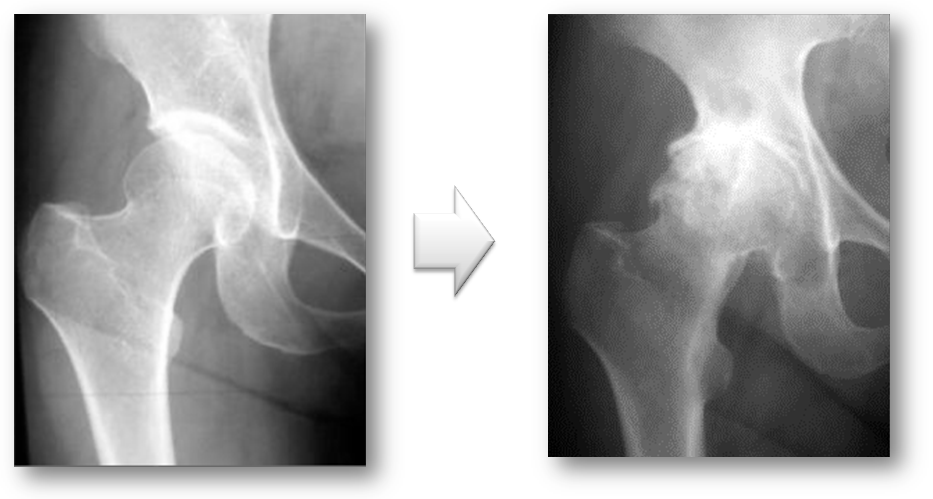

変形性股関節症には、一次性と二次性があります。一次性は、長い年月を経てあるいは関節の使いすぎによって軟骨が消耗して起こります。二次性は、乳児期の股関節の脱臼や発育不全などの臼蓋形成不全によって早期から起こる変形性股関節症です。

レントゲンで見ると一次性は、正常な股関節が長い年月や股関節の使い過ぎによって軟骨が消耗して変形性股関節症が発症します(図7)。二次性は、元々臼蓋形成不全により体重がかかる部分が限られており早期なら軟骨が消耗し変形性股関節症になります(図8)。

図7. 一次性の変形性股関節症

長い年月を経て、あるいは関節の使いすぎによって起こる。

図8. 二次性の変形性股関節症

乳児期の股関節の脱臼や股関節の発育が悪いこと(臼蓋形成不全)が原因で起こる。